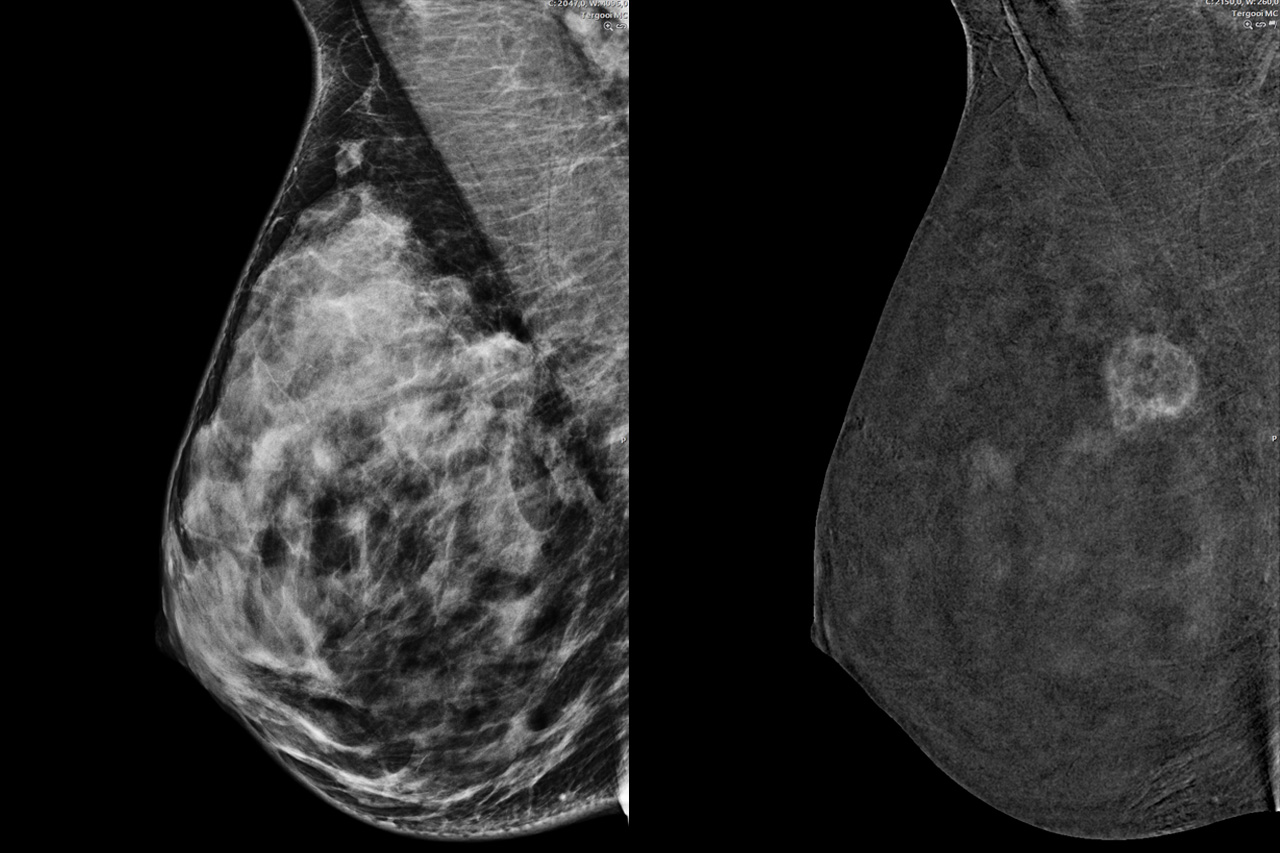

De eerste schakel is radiologie. Van Keulen zit samen met collega Pien van Dijk in een donkere kamer achter grote computerschermen mammografieën te bekijken die net door radiodiagnostisch laboranten zijn gemaakt. Van Keulen legt uit dat er verschillende soorten foto’s gemaakt kunnen worden. ‘Eerst wordt er een 3D-mammografie gemaakt; daarmee kunnen we laagje voor laagje de borst bestuderen. Maar vooral bij veel (wit) klierweefsel zien we vaak minder goed waar een mogelijke afwijking precies zit. Het zijn witte plekjes tegen een witte achtergrond. Daarom gebruiken we ook een andere techniek: een mammografie met contrastvloeistof. Daarbij wordt de achtergrond van de borst donker en springt de witte afwijking eruit. Zo kunnen we goed zien of het om een tumor of een cyste gaat.’